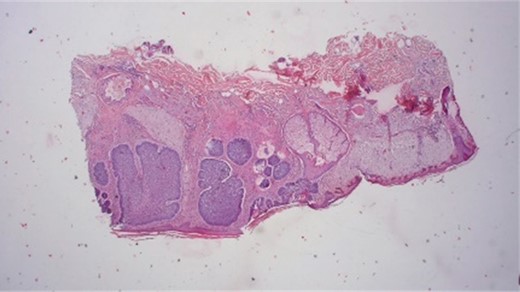

After a 3-month healing period, the area exhibited healthy skin without signs of cancer relapse [Fig. 9]. Immunohistological analysis post-Mohs excision confirmed the infiltrative growth of tumor cells, diagnosing BCC, which was excised with a safety range of at least 1 mm (Fig. 10).

Histological results provide typically nesting patterns composed of proliferating basaloid cells. Basaloid cells arrange themselves in a palisading pattern at the periphery of the nests. This palisading is a key histological feature and is often linked to a picket fence appearance. The stroma surrounding the nests typically show variable degrees of fibrosis and inflammation. This fibrotic stroma may contain collagen fibers, and the inflammatory infiltrate may consist of lymphocytes and histiocytes (Dr.Jäkel, Pathologie Bremen, Bremen).